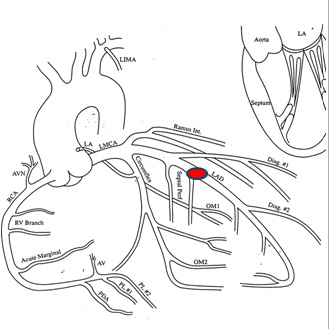

Figuur 3: Schematische weergave van de coronaire vaatboom. Met een rode stip is aangegeven waar de occlusie zich bevindt.